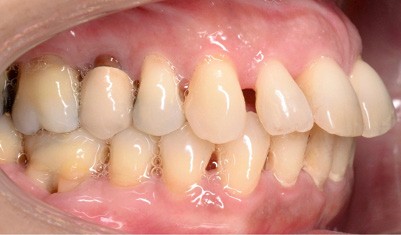

À l’examen endo-buccal (fig. 2), on note une formule dentaire complète (absence des 8) avec présence de restaurations multiples étanches, un bon contrôle de plaque et une parodontite de stade 4 grade C stabilisée [3], des récessions gingivales et des mobilités dentaires généralisées (degré 2, classification de Miller). L’arcade mandibulaire présente une courbe de spee importante avec égression du bloc incisivo-canin. Les milieux inter-incisifs sont alignés, le recouvrement est normal, le surplomb est augmenté à 3 mm et associé à des diastèmes et de la vestibulo-version des incisives maxillaires. Les relations antéro-postérieures canine et molaire sont en Classe I d’Angle.